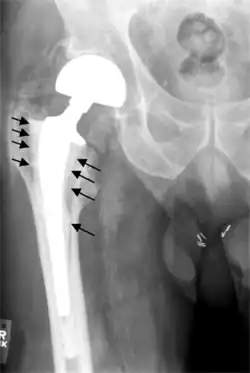

Loosening

Hip prosthesis displaying aseptic loosening (arrows)

Hip prosthesis zones according to DeLee and Charnley,[43] and Gruen.[44] These are used to describe the location of for example areas of loosening.

On radiography, it is normal to see thin radiolucent areas of less than 2 mm around hip prosthesis components, or between a cement mantle and bone. These may indicate loosening of the prosthesis if they are new or changing, while areas greater than 2 mm may be harmless if they are stable.[45] The most important prognostic factors of cemented cups are absence of radiolucent lines in DeLee and Charnley zone I, as well as adequate cement mantle thickness.[46]